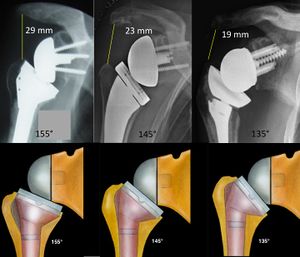

The neck-shaft angle is one of the biggest variabilities between different prosthesis designs. A steeper or more anatomic neck-shaft angle (Grammont-type 155 degrees vs. 145 degrees and 135 degrees designs) leads to a decrease in the acromiohumeral distance. For every 10 degrees decrease the acromiohumeral distance shortens by approximately 3 mm. In other words, between a 155 degrees and a 135 degrees configuration, arm lengthening varies by about 10 mm.

Range of motion after reverse shoulder arthroplasty: which combinations of humeral stem and glenosphere work the best?

Reproduced from Lädermann et al., with permission.[40]

Neck-shaft angle (inclination)

The Grammont reverse shoulder arthroplasty was designed as a non-anatomic implant with a relative valgus humeral neck inclination of 155 degrees. Based on the work by Gutierrez et al.,[35] neck-shaft angle has decreased in modern prosthetic designs to a more varus or anatomic inclination of 145 or 135 degrees.

The neck shaft angle is a major factor influencing length of the arm,[18] but has little effect on humeral lateralization; by changing inclination from 155 degrees to 135 degrees within an onlay design, humeral offset only increased by about 2 mm.[70]

Theoretically, compared to low neck shaft angle stems, higher inclinations (155 degrees) increased abduction by 100% and external rotation in abduction, regardless of glenosphere designs.[70][24] This finding is important as such external rotation is a major factor in the ability to perform activities of daily activities such as hair care and facial grooming. However, a 155 degrees is associated with decreased adduction external rotation at the side[70][72][55] and extension due to medial bony impingement (which also leads to scapular notching).[24][39][46][55][73][74] Lateralization obtained via a lower neck shaft angle increases adduction, by 357% between a 155 degrees prosthesis compared with a 135 degrees prosthesis. Also, an increase in extension, of 381%, and external rotation elbow at side, of 116%, are observed with a 135 degrees prosthesis.[70] Such finding are important as external rotation with the elbow at the side and extension led to friction between the scapular pillar and the polyethylene insert. Even if this friction phenomenon does not limit range of motion, it likely contributes to progressive polyethylene wear and scapular notching.[63] Reducing the neck-shaft angle can, however, have some negative effects on reverse shoulder arthroplasty contact mechanics. The contact area is reduced by 29% for 155 degrees to 145 degrees and by 59% for 155 degrees to 135 degrees. Consequently, there is an increased maximum contact stress by 71% for 155 degrees to 145 degrees and by 286% for 155 to 135 degrees.[75]